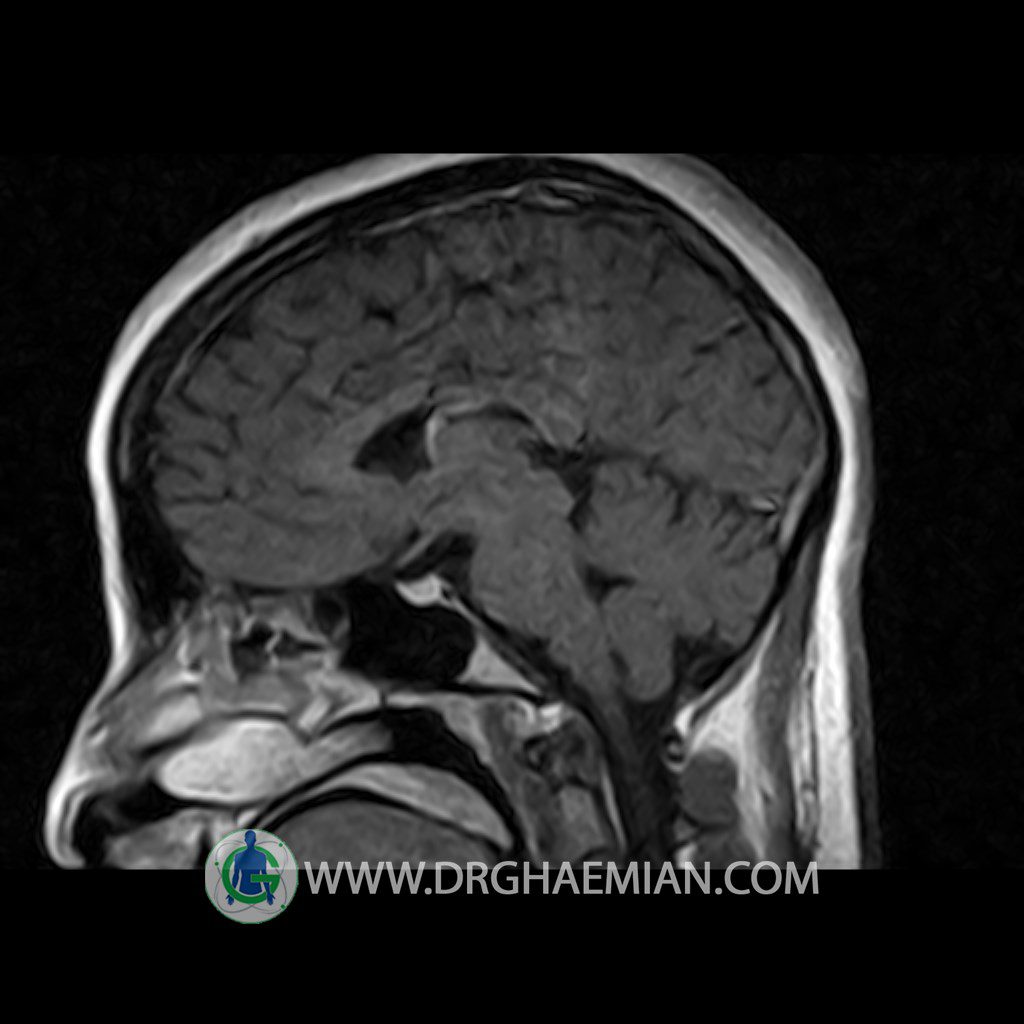

Technique: Axial , coronal T1 , Axial , coronal , sagittal T2 , Axial, coronal T1 post Gd & 64 dynamic thin coronal slices.

The pituitary tissue shows normal , position, shape , size and homogeneous signal intensity both before and after contrast administration .

Anterior and posterior pituitary gland were normal .

It contains no circumscribed hypointense or hyperintense areas .

The infundibulum is centered and of normal size .

The optic chiasm and suprasellar spaces appear normal .